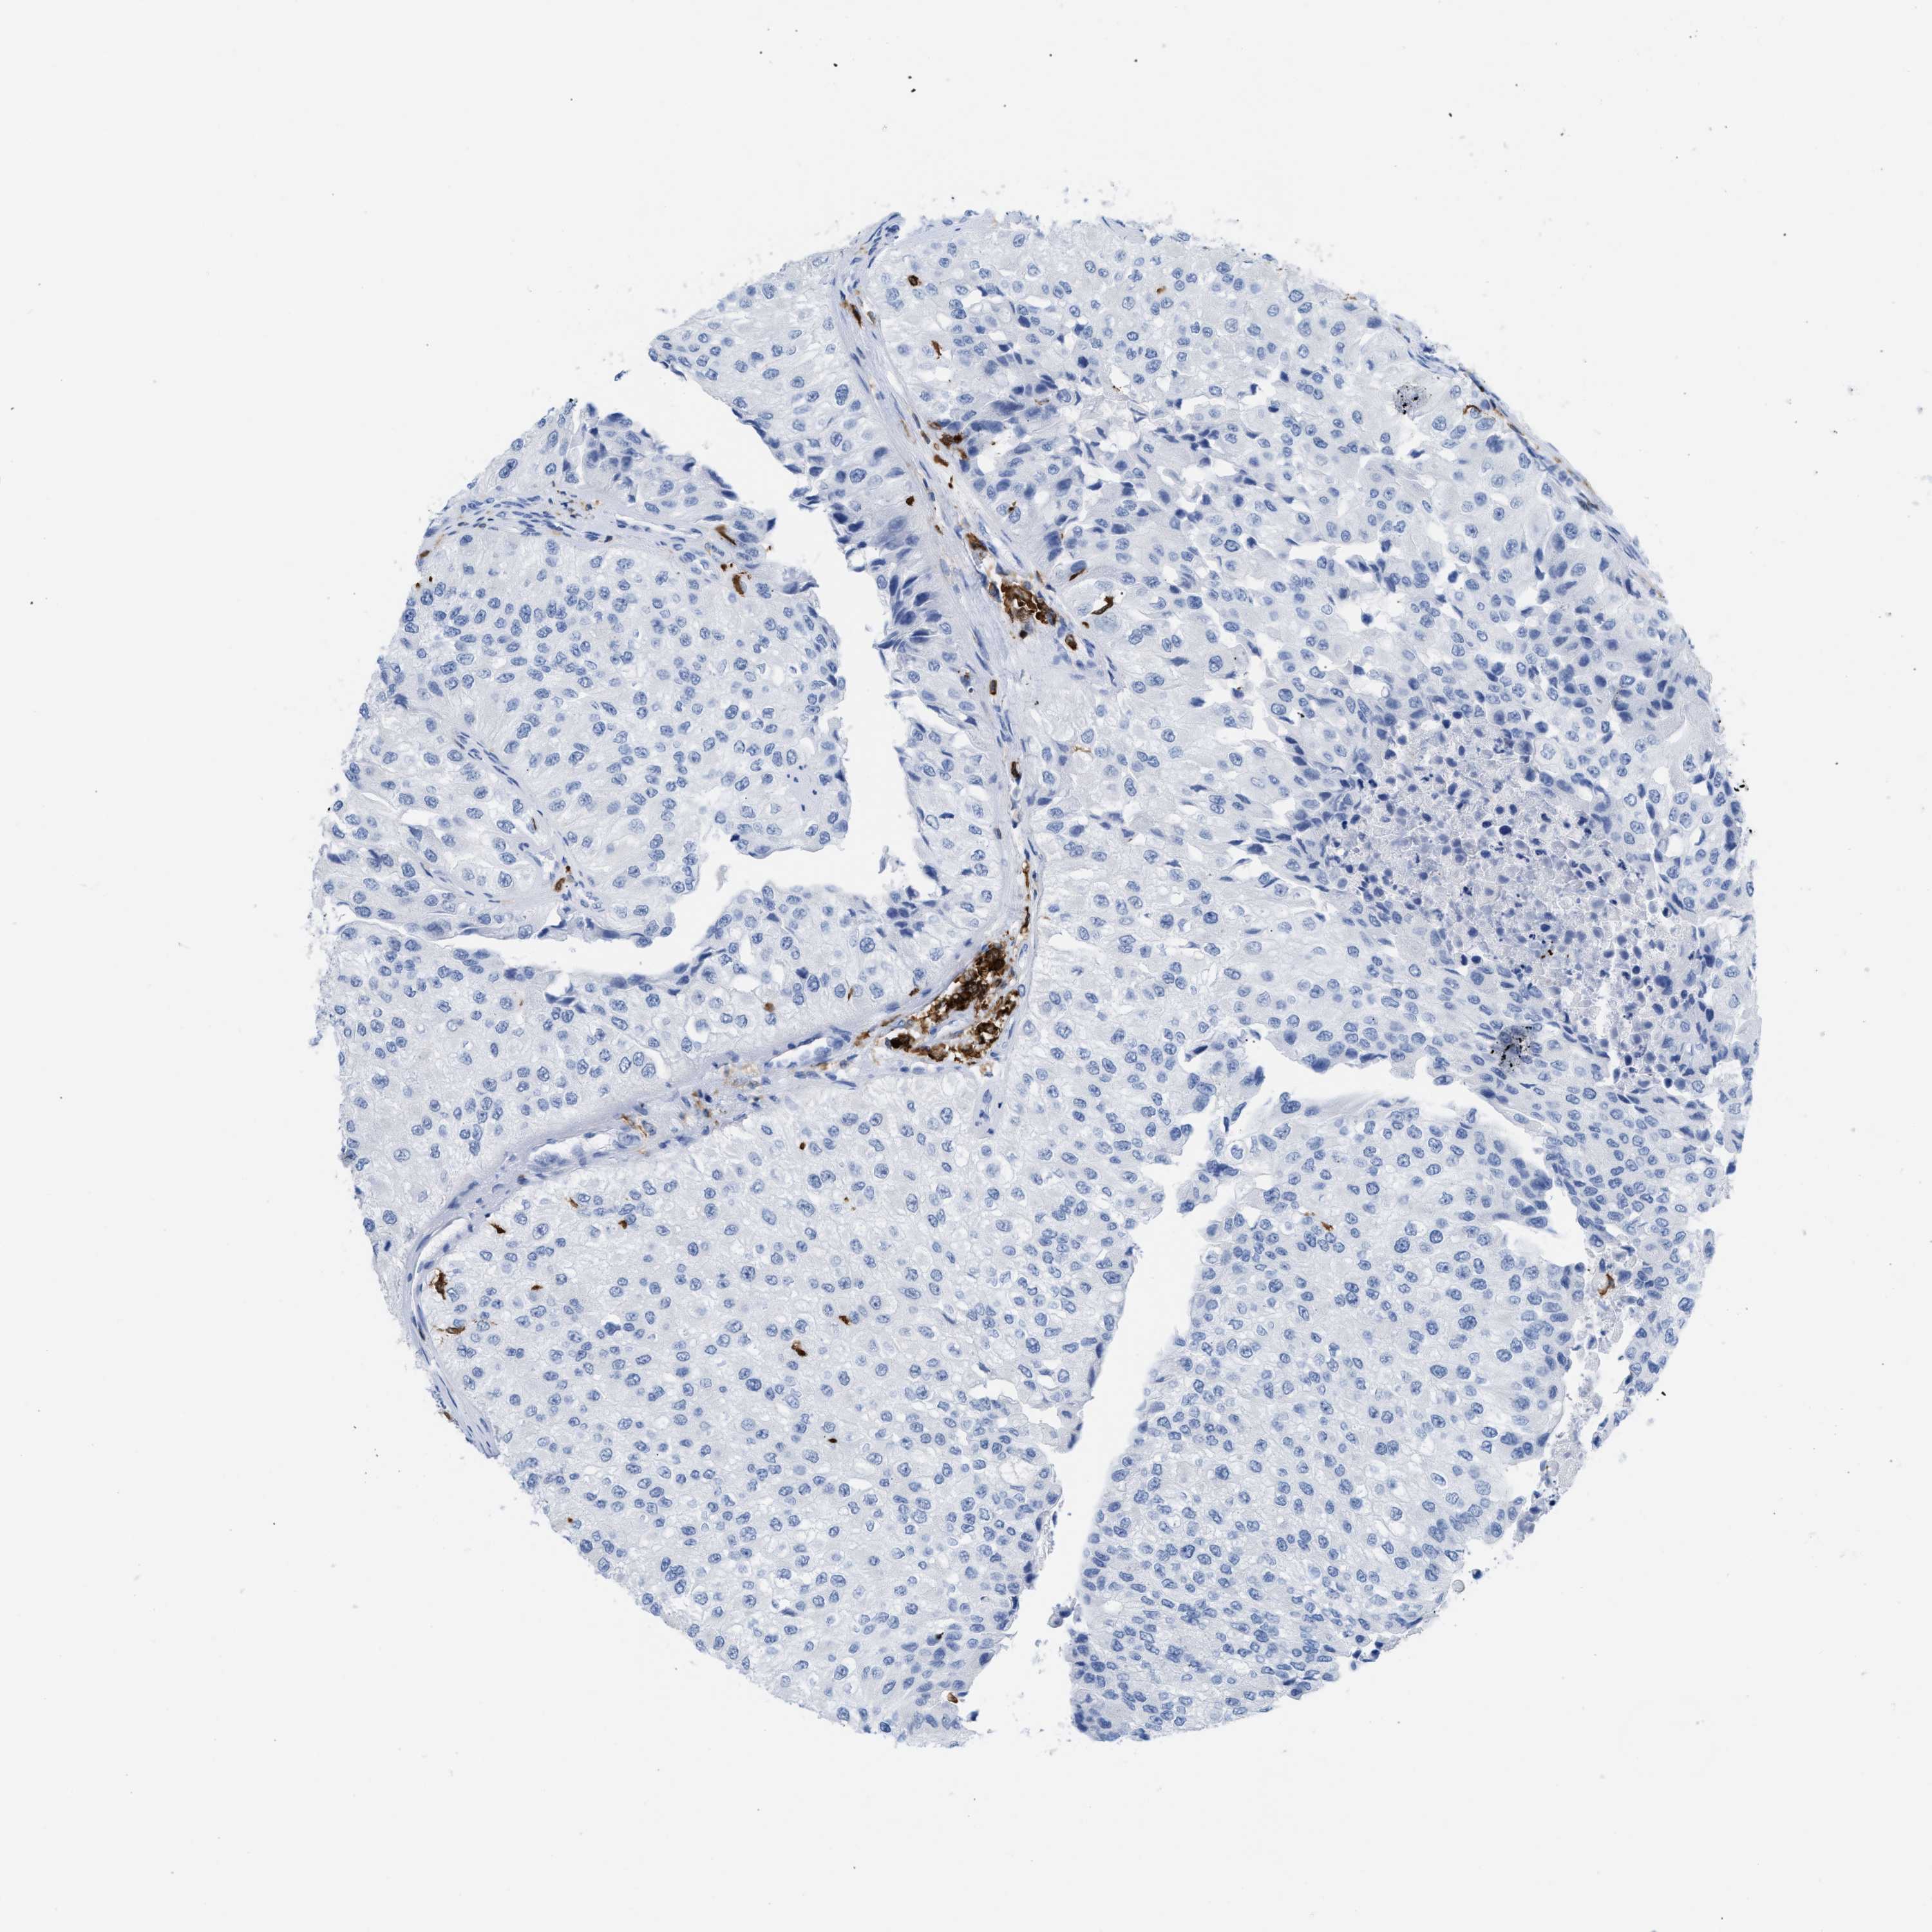

UROTHELIAL CANCER - Protein expressioni

A mouse-over function shows sample information and annotation data. Click on an image to view it in a full screen mode. Samples can be filtered based on level of antibody staining by selecting one or several of the following categories: high, medium, low and not detected. The assay and annotation is described here.

Antibody stainingi

Antibody staining in the annotated cell types in the current human tissue is reported as not detected, low, medium, or high, based on conventional immunohistochemistry profiling in selected tissues. This score is based on the combination of the staining intensity and fraction of stained cells.

Each image is clickable and will lead to virtual microscopy that enables deeper exploration of all samples and also displays staining intensity scores, fraction scores and subcellular localization as well as patient and tissue information for each sample.

Antibody CAB020673

Urothelial carcinoma, Low grade

Urothelial carcinoma, High grade